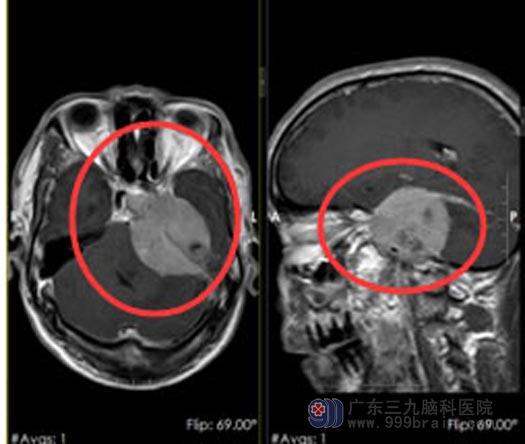

入住神经外五科进一步头颅MRI检查,结果:1.左侧中后颅窝占位性病变,病灶大小约52mm×47mm×50mm,考虑脑膜瘤可能,待排孤立性纤维瘤/血管周细胞瘤;2.脑白质散在变性灶;3.右侧侧脑室稍扩张,脑室旁少许间质水肿;4.左侧大脑镰下疝(轻度);CTA检查示:左侧跨中后颅窝占位性病变,血供较丰富,考虑脑膜瘤可能,邻近左侧颈内动脉虹吸部受包埋并明显变细。

颈内动脉被肿瘤包绕,手术复杂程度可想而知,要想提升肿瘤切除率就必须使主要供血血管(颈内动脉)可以连同肿瘤一并切除,然而阻断颅内主要供血动脉,即使术前通过颈内动脉闭塞试验,在颈内动脉闭塞后,发生脑梗死的风险及死亡风险依然存在。神经外五科治疗团队反复讨论研究,缜密地制定了手术方案:在切除肿瘤的同时行搭桥术。为了解对侧代偿情况,随后为石叔行颈内动脉闭塞实验及全脑血管造影术,影像显示:左侧颈内动脉岩骨段及海绵窦段移位,管腔狭窄,考虑占位推挤,另压颈试验示前交通及左侧后交通开放,双侧Allen test(-)。